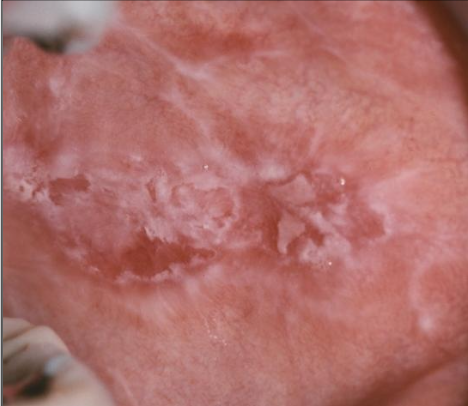

White lace-like striations (Wickham striae), maybe erythematous, bleeding

What is reticular lichen planus?

More common, asymptomatic, lace-like (Wickham striae)

What is erosive lichen planus?

Not as common, painful, erythematous, bleeding